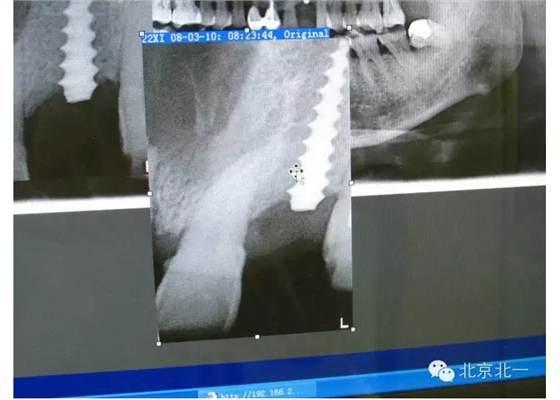

擅長(zhǎng):種植外科,尤其專長(zhǎng)復(fù)雜牙種植,自體骨移植同期種植,上頜竇底內(nèi)外提升同期種植技術(shù),美學(xué)區(qū)種植技術(shù),即刻種植外科與即刻負(fù)重技術(shù),軟組織成形外科種植技術(shù)及全口無牙頜ALL-ON-FOUR技術(shù),種植并發(fā)癥和種植急癥處置等手術(shù)治療,從事口腔頜面外科,正頜外科、頜面部整形、微創(chuàng)拔牙,笑氣無痛舒適種植十余年。